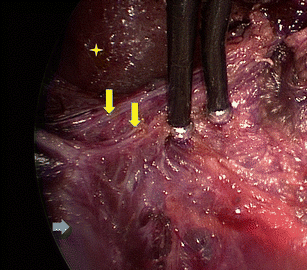

Sparing the extrinsic autonomic innervation of the internal anal sphincter during total mesorectal excision is important for the preservation of anal sphincter function. This study electrophysiologically confirmed the topography of the internal anal sphincter nerve supply during laparoscopic-assisted transanal minimally invasive surgery for total mesorectal excision.

This prospective study was conducted at two large multispecialty referral centers. Six patients (five males and one female) aged between 45 and 65 years with low rectal cancer (≤5 cm from the anal verge) were enrolled. Surgery was performed under electric stimulation of the pelvic autonomic nerves with observation of the electromyographic signals of the internal anal sphincter.

The minimally invasive transanal surgical approach enabled advantageous visualization of the pelvic autonomic nerves in all patients. In particular, extrinsic innervation to the internal anal sphincter near the levator muscle was consciously spared under electrophysiological confirmation. The evoked absolute electromyographic amplitudes of the internal anal sphincter during transanal minimally invasive surgery were significantly lower than the initial results of the laparoscopic approach [3.7 μV (interquartile range 2.4; 5.7) vs. 4.3 μV (interquartile range 3.1; 8.6); p = 0.002]. Five key zones of risk for pelvic autonomic nerve damage were identified. No complications occurred.

The electromyographic results of this preliminary study indicate advantages for sparing the internal anal sphincter innervation during transanal minimally invasive mesorectal dissection considering the specific in situ neuroanatomical topography.